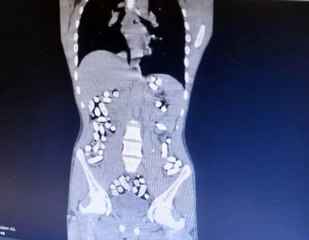

- Midesinde uyuşturucu sevkiyatı yapan zanlı tutuklandı 1 kilo uyuşturucuyu yutarak taşıyan İran uyruklu zanlı Erzincan'da yakalandı Erzincan'da narkotik polislerinin yaptığı yol uygulaması sırasında durdurulan otobüste, uyuşturucuyu midesine gizleyen İran uyruklu 1 kişi tutuklandı. br- Midesinde uyuşturucu sevkiyatı yapan zanlı tutuklandıbr 1 kilo uyuşturucuyu yutarak taşıyan İran uyruklu zanlı Erzincan'da yakalandıbrERZİNCAN - Erzincan'da narkotik polislerinin yaptığı yol uygulaması sırasında durdurulan otobüste, uyuşturucuyu midesine gizleyen İran uyruklu 1 kişi tutuklandı. Tutuklanan zanlının bedeninden 1 kilo 198 gram Afyon Sakızı ele geçirildi. br Erzincan İl Emniyet Müdürlüğü Narkotik Suçlarla Mücadele Şube Müdürlüğü ekiplerince uyuşturucu madde kuryeliği yapan şahıslara yönelik İran otobüsleri üzerinde yapılan uygulamada; İran otobüsünde yolculuk yapan Abdulmennan S. Haberabr br hbrlr1.